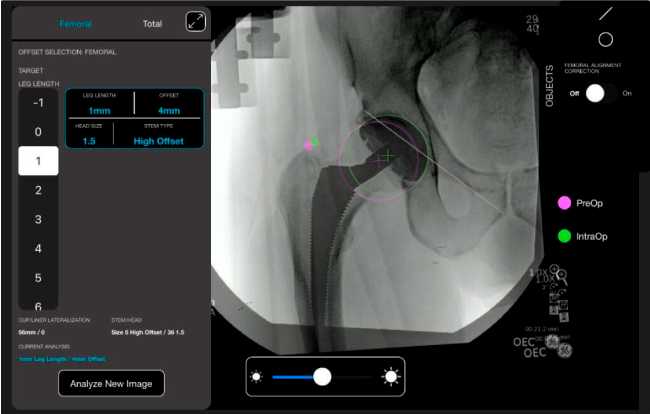

Mayor nivel de información intraoperatoria facilita la colocación correcta de los implantes:

• Desplazamiento y offset para posicionamiento óptimo del componente (vástago) femoral.

• Verificación de la posición deseada del implante que potencialmente puede ayudar a reducir la probabilidad de dislocación protésica y aumentar la estabilidad de la articulación.

• Anotaciones digitales y herramientas de análisis de longitud de pierna.

• Con tecnología ONETRIAL® que calcula automáticamente el cambio en la longitud de la pierna y el desplazamiento para todas las combinaciones de implantes en una tabla fácil de leer.